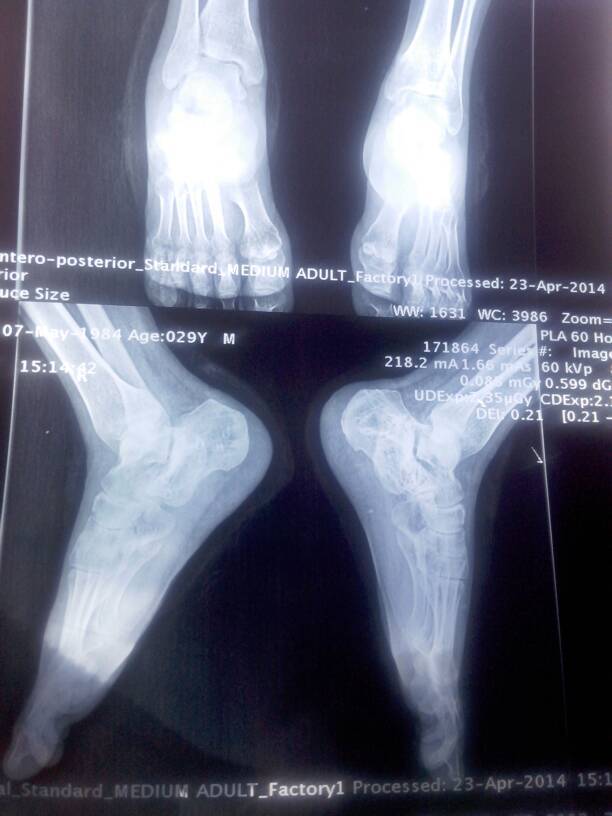

脚根骨骨折手术做了五个月多了还是出现软组织肿胀疼痛,怎么办啊?而且走路走上10来分钟脚底板就痛,早上起来切口处有针刺感,咋办呀?求好的骨科医生帮帮我!附带了钢板取出手术后三个月的片子!

病情分析: 您好,骨折五个月时间,骨头愈合还是很好的,出现肿胀疼痛,一般是血液循环不佳,软组织粘连所致 指导意见: 一个是需要加强锻炼,二是结合中药熏洗治疗,还可以结合理疗,按摩等等治疗,效果不错,逐渐就会恢复正常的,一般不会有大问题